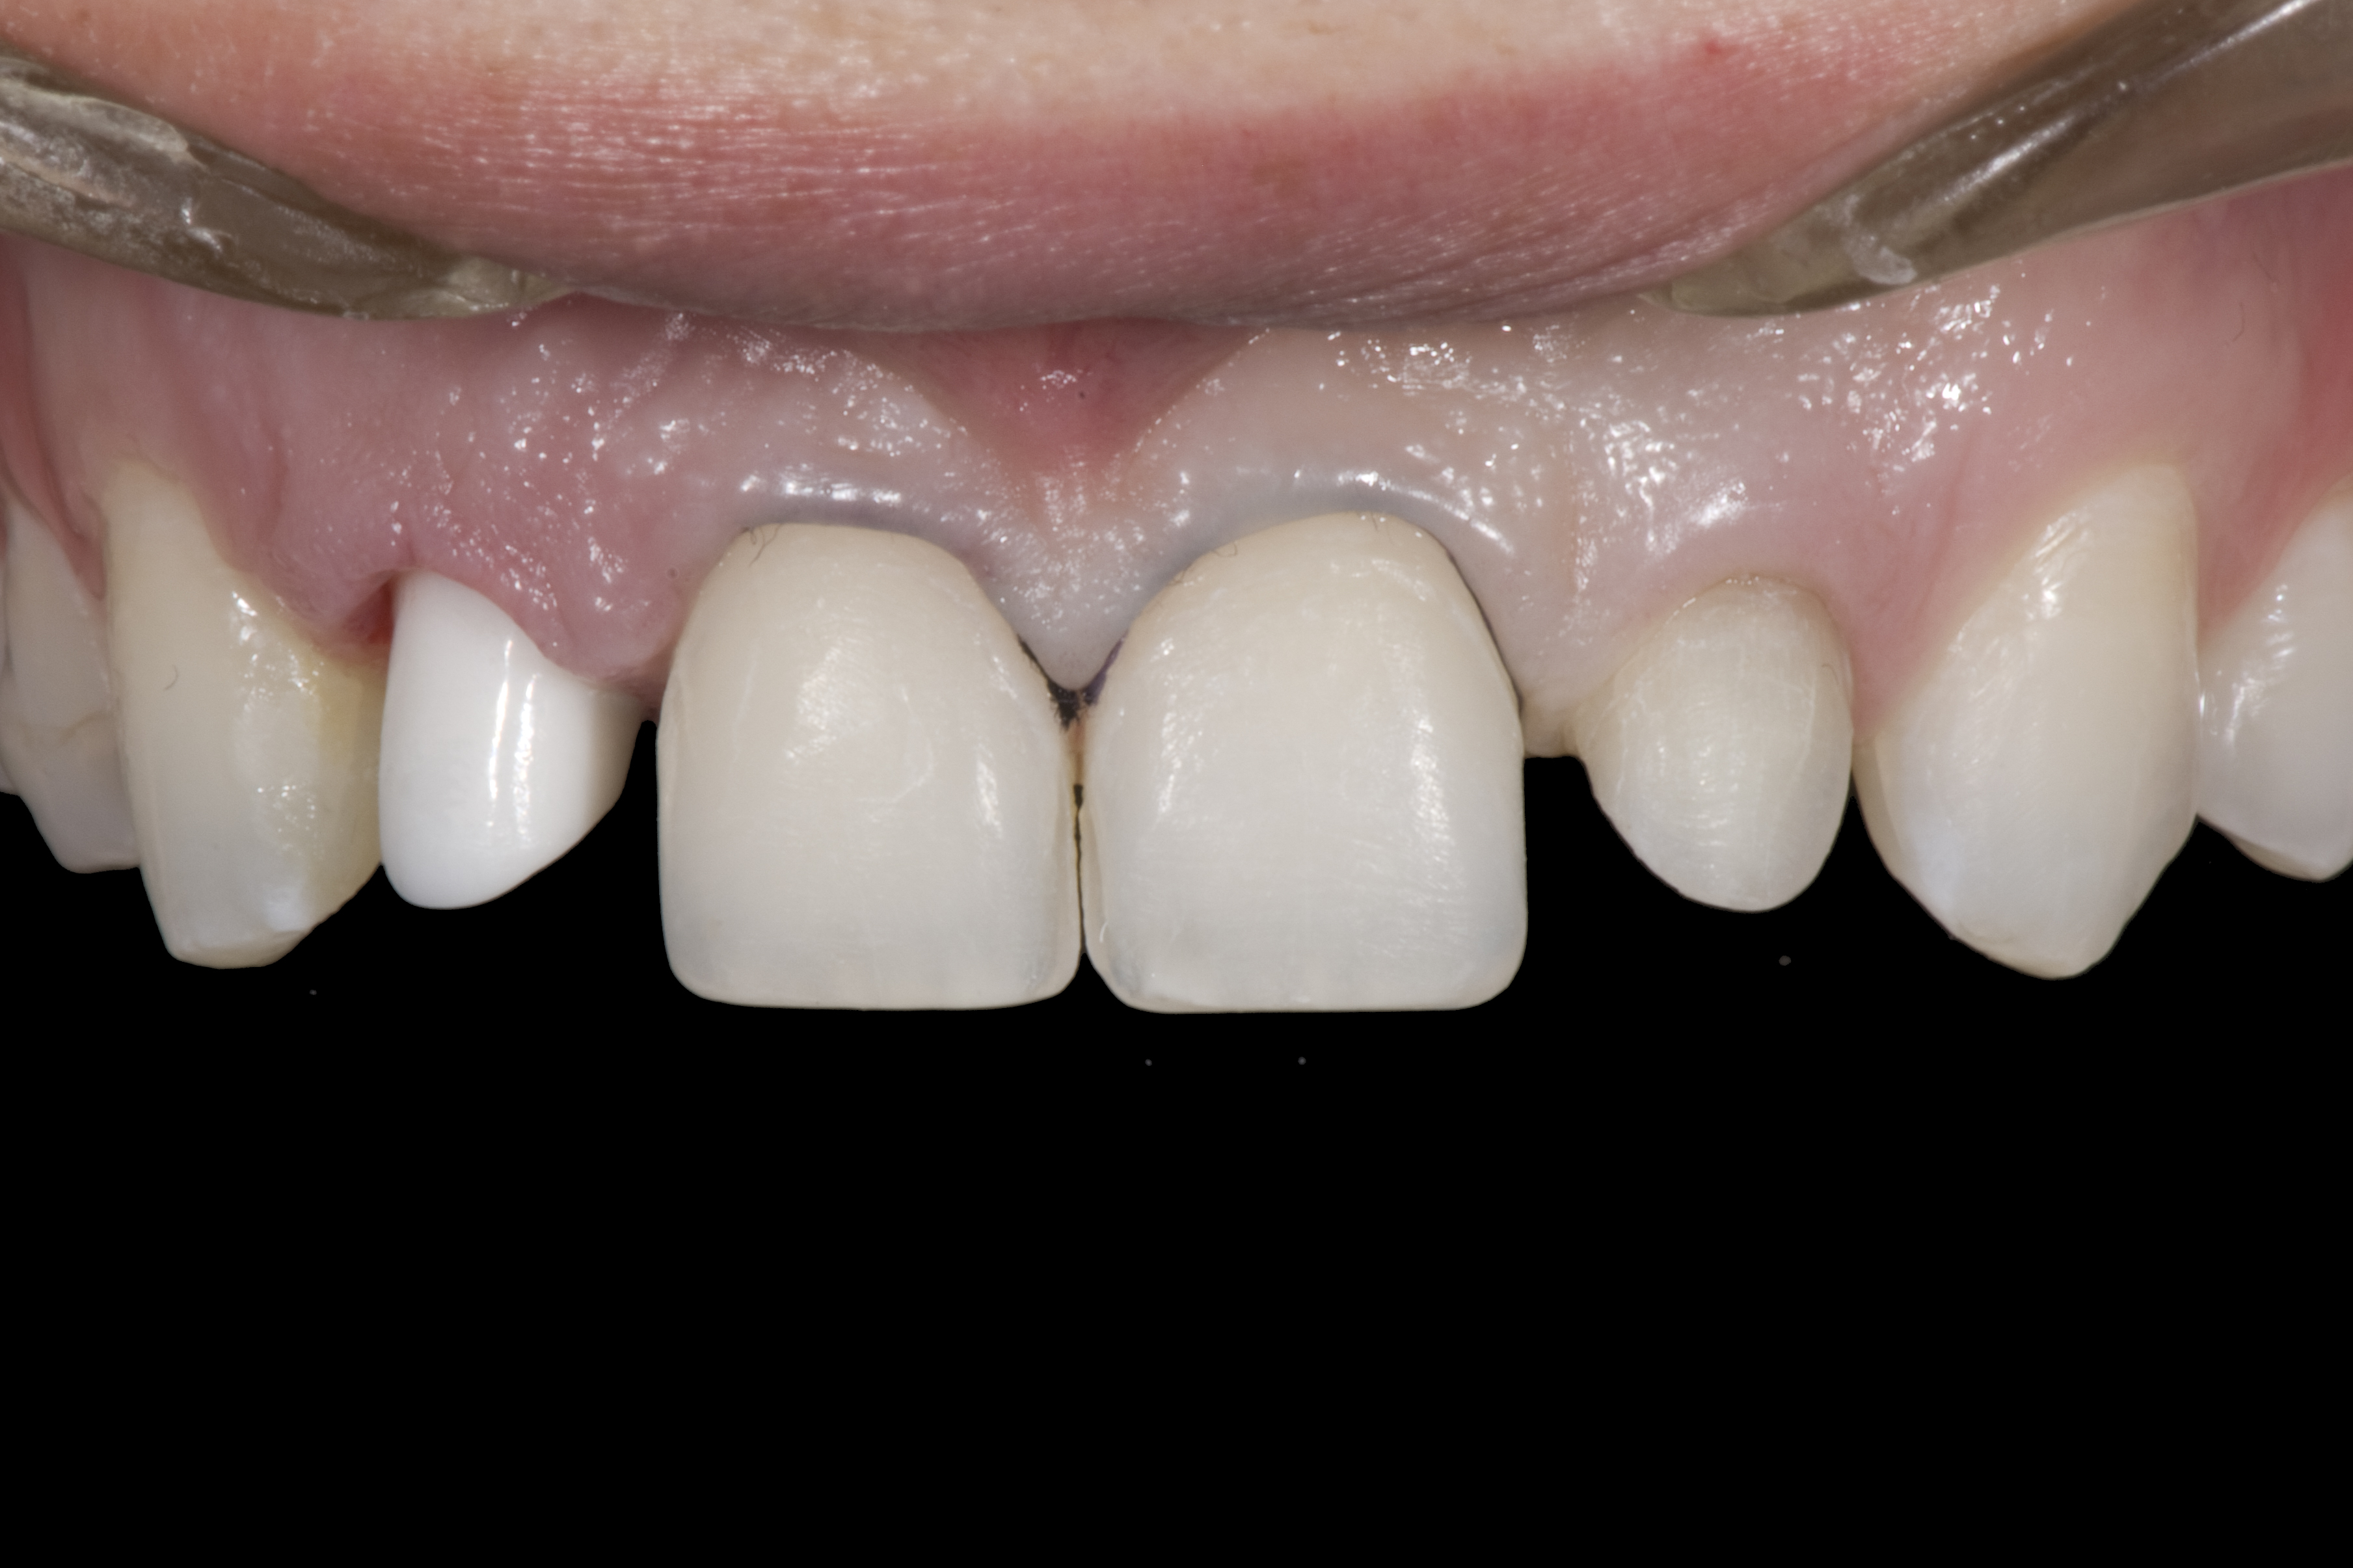

(12.) 15-year-old girl after orthodontic therapy idealized maxillary lateral incisor spaces.

Figure 12

Some patients do not want an implant due to the need for surgical intervention, and others may not have enough space for implant placement. A 15-year-old patient presented to the office after completion of orthodontic treatment to idealize the spacing of her teeth and improve her occlusal relationship (Figure 12 through Figure 14). Because both of her maxillary lateral incisors were missing, the patient was wearing a retainer with lateral incisor pontics. She had a busy school schedule, but expressed her desire for a fixed restorative option. All of her options were discussed, and the patient was informed that if she wanted an implant, she would have to wait for at least 3 to 4 years for completion of growth. The patient was not sure if or when she wanted to have an implant placed in the future, especially considering her busy schedule and desire to attend college after high school. Considering her age and the need to be conservative, a single-wing zirconia Maryland Bridge was chosen as the ideal prosthetic replacement option. Because bonding a non-etchable and smooth surface such as zirconia requires chemical adhesion, it was decided to use a modified technique to make the bridge more retentive. One of the ways to improve adhesion of a zirconia bridge is to use an etchable feldspathic ceramic layer on the internal surface of the zirconia retainer.56-58 Unfortunately, it can be difficult to determine the thickness of the ceramic and ensure accurate seating of the restoration.

When the patient returned, the fit was evaluated in the mouth. Once verified, the internal surface of the framework was etched with a 9.5% hydrofluoric acid for 90 seconds and then salinized. After etching the enamel surface with phosphoric acid for 30 seconds and applying the primer (Single Bond Plus, 3M ESPE) to both the internal surface of the framework and the enamel, the zirconia bridge was bonded with a dual-cure resin cement (RelyX™ ARC, 3M ESPE). After the procedure, the patient ended up with a long-term, high-strength esthetic restoration advantaged by the bonding potential of fledspathic ceramic (Figure 20 through Figure 24). Six years after placement, the prosthesis had remained in place with no complications.